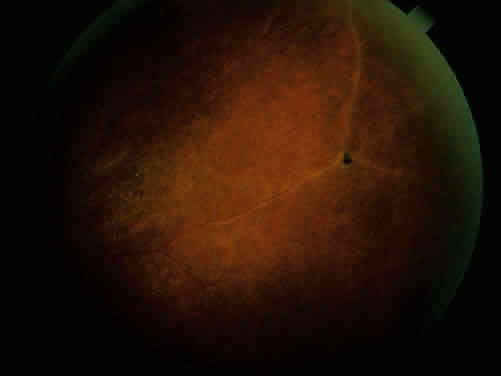

The acute iridocyclitis is suggestive of vascular occlusive changes, or acute tissue damage, with sudden onset and massive outpouring of cells into the anterior chamber or vitreous (Fig. 10). Vascular injection is not as pronounced as the number of cells in the anterior chamber or vitreous would suggest, and protein in the anterior chamber may be minimal. The cells settle to the dependent portion of the anterior chamber, forming a hypopyon. There may be little tendency toward formation of keratic precipitates. The process may be unilateral or bilateral. Episodes usually are recurrent, and recurrences produce increased tissue damage, progressing to more chronic involvement. All vascular tissues of the eye may become involved, including episcleritis, scleritis, iridocyclitis, retinal and choroidal vasculitis, and optic neuritis. Retinal focal ischemic areas of edema and optic nerve edema (Fig. 11) are seen in the acute phases, and retinal and optic nerve atrophy along with retinal pigment epithelial changes resembling secondary retinitis pigmentosa, attenuation, and sheathing of retinal vessels are seen in the later stages of ocular involvement.76,91–93

Fig. 11. Optic nerve and retinal edema with cells in the vitreous in posterior involvement with acute Behçet's disease.